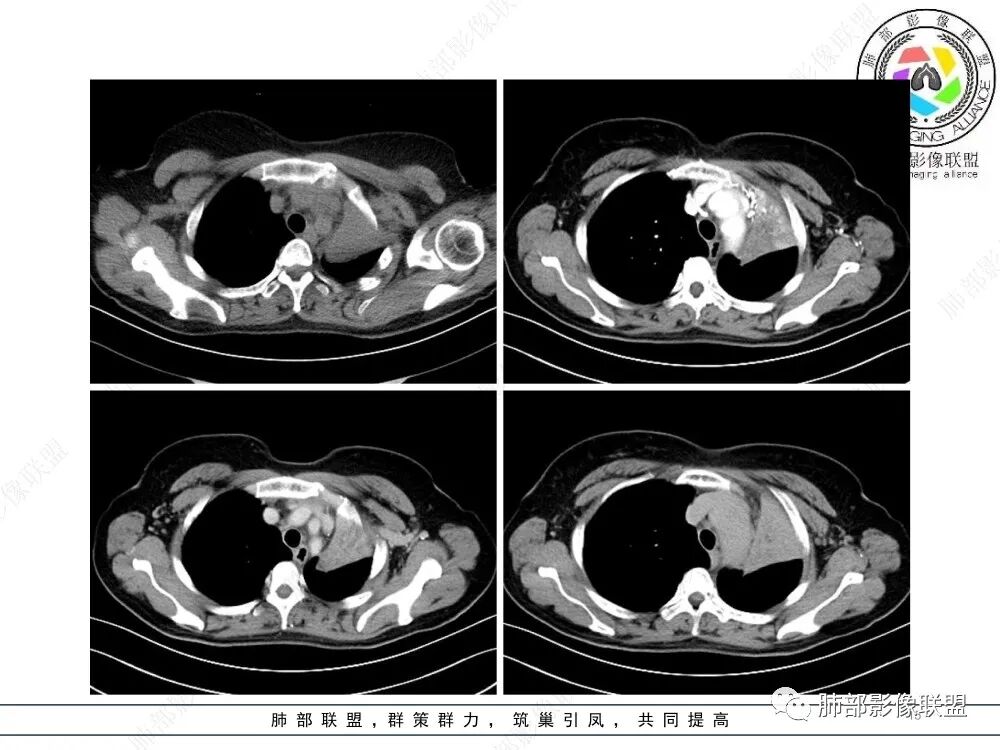

2、影像表现:正常肺背景,左肺上叶支气管腔内占位,上叶支气管截断,远端肺组织不张,强化差异衬托出肺门区结节影或块状影。增强扫描腔内占位轻中度不均匀强化,可见坏死,远端粘液栓,局部肺动脉受压、侵犯,纵膈淋巴结无明显肿大,无胸腔积液。

3、综合分析:老年女性,支气管腔内占位明确,病灶向周围侵犯,诊断恶性肿瘤并肺不张问题不大。需要考虑到的疾病谱有鳞癌、腺样囊性癌、粘液表皮样癌、类癌、小细胞肺癌等。

④小细胞肺癌属于高度恶性神经内分泌肿瘤,好发于吸烟男性,多数小细胞癌影像表现较典型,表现为肺门旁或外周边缘膨隆、边界清楚的软组织结节或肿块,由于肿瘤组织坏死不彻底,常表现为“沼泽样”坏死区,较早出现肺门和纵膈淋巴结转移,有“娘小崽大”的特点。纵隔淋巴结融合,可形成“冰冻纵膈”。小细胞癌侵袭力强,容易包埋血管形成“血管包埋征”,肿瘤沿支气管浸润时可见病灶呈鸭蹼和腊肠样凸起,相较于鳞癌而言,小细胞癌导致的阻塞性肺炎常常较轻,较少合并肺不张,少见合并胸水。

就本例而言,患者为女性,无肺气肿背景,未提及吸烟史,影像上强化程度偏轻,未见湖泊样坏死,尽管中央型肺癌中以鳞癌最多见,且造成完全阻塞及肺不张,但在女性患者诊断鳞癌仍需谨慎。支气管腔内结节,强化程度轻,涎腺肿瘤需要考虑,不典型类癌也不能除外。女性患者,未提及吸烟史,尽管未见纵膈淋巴结明显肿大,但支气管明显相关,小细胞肺癌亦应当重点排除。